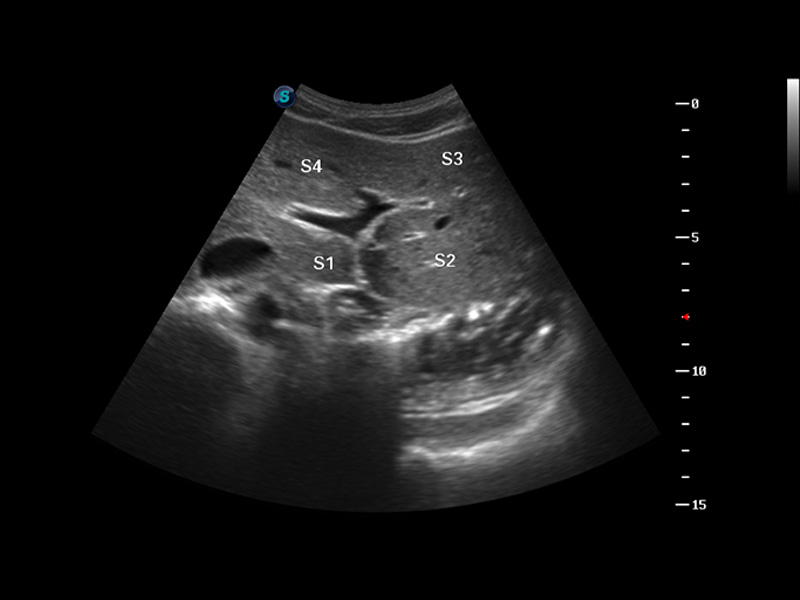

S8 EXP便携式彩色多普勒超声诊断仪是DB中国旗舰官方网站研发的高端全身应用型便携彩超。高通道的VIS平台融合可视化(Visual)、智能化(Intelligent)和人性化(Smart)的特点,配以DB中国旗舰官方网站自主研发生产的探头大家族,使您能够快速、准确的获得病人信息,提高工作效率的同时减轻疲劳。

多波束形成器

μ-Scan微米成像

3D/4D成像